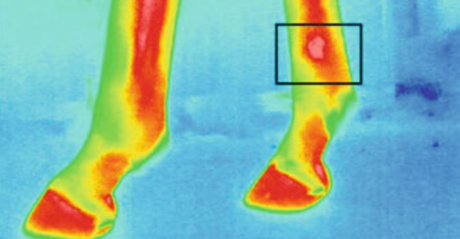

圖為動物測溫儀的馬蹄熱成像

屠宰前動物的壓力水平對肉質至關重要。壓力水平與動物的血液和體溫相關。因此,重要的是監(jiān)視并應對例如溫度升高的溫度。在運輸過程中,測量豬耳朵的溫度,發(fā)現(xiàn)溫度與皮質醇的濃度和肌酸激酶的活性呈正相關。例如,診斷馬匹的行走時,動物測溫儀熱成像會很有用。建議使用熱成像來檢測炎癥和其他異常情況,特別是在馬的腿和蹄中。并且也已經進行了對諸如蛙等外熱動物的熱力學特性的分析。測量了從8℃(人工冬眠)到23℃(人工喚醒)加熱過程中青蛙不同身體部位的溫度。在這樣的實驗中,動物測溫儀進行測量而不會傷害或接觸動物是一個很大的優(yōu)勢。